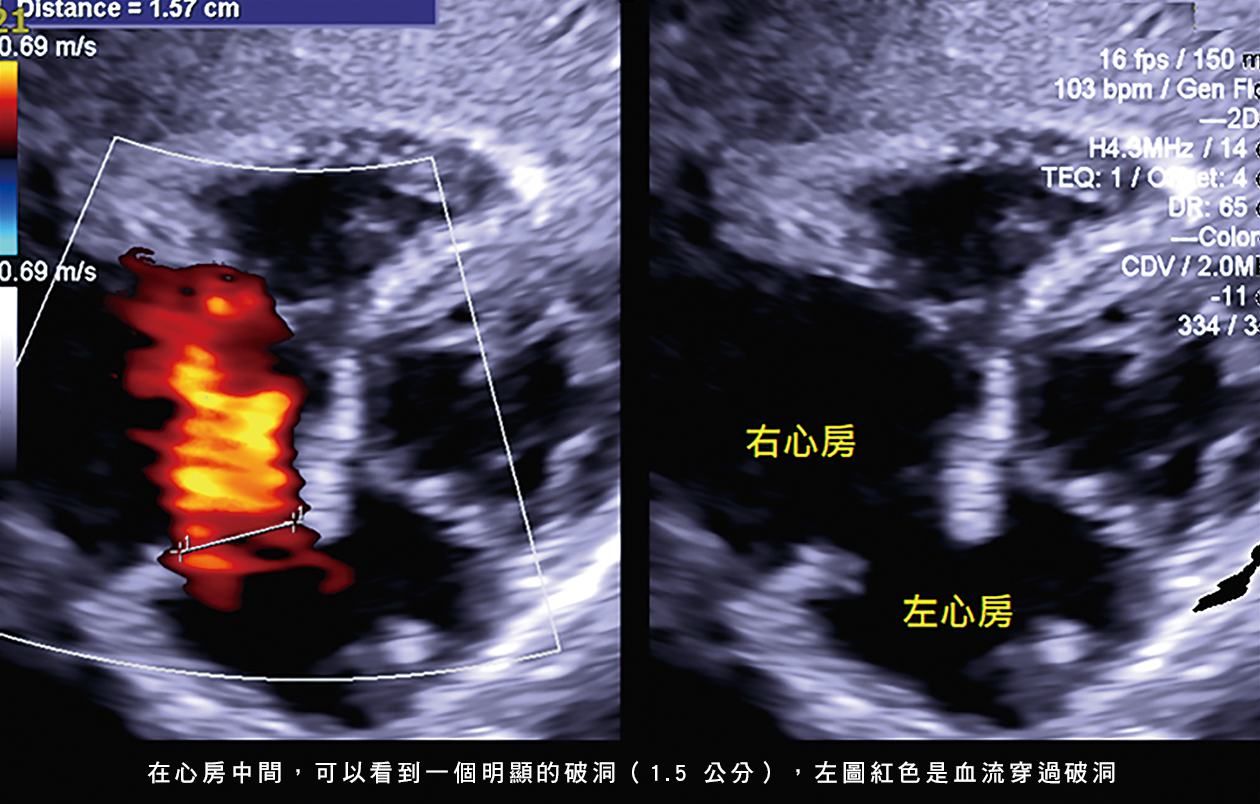

由於醫學科技的進步和診斷率的提高,許多小兒先天性心臟病現今已經可以使用心導管的方式治療,這些心臟病包括:心房中膈缺損、心室中膈缺損、開放性動脈導管、還有肺動脈狹窄。以往如果是複雜的心臟構造問題,經常會需要使用到全身麻醉的方式,搭配食道超音波在手術中去檢查心臟。但是近年來由於超音波發展的進步,以及經驗的累積,有許多心導管手術已經可以使用局部麻醉(奇美醫院主要是採取這個做法),再結合止痛藥和鎮靜藥,就可以讓小病人在手術過程中保持安靜和不感到太多疼痛。過程中,會使用血管內超音波或者是胸前超音波去監測過程,如此一來就可以完成手術了。所以,止痛和鎮定藥物的使用就顯得重要。

心導管治療和檢查,簡單說就是在大腿內側的血管打兩個針,沿著血管把無菌的管子送到心臟,再去各個地方量測壓力,有的時候還會用顯影劑照相。當檢查做完,就可以針對問題去治療了。像是心房或心室中膈缺損,就可以用關閉器把缺損塞起來。手術結束後,只有那個關閉器會留在心臟,其他的導管和導線都會移除,手術後大腿只會留有兩個針孔,也不用縫合,通常換藥個幾天就會癒合了。